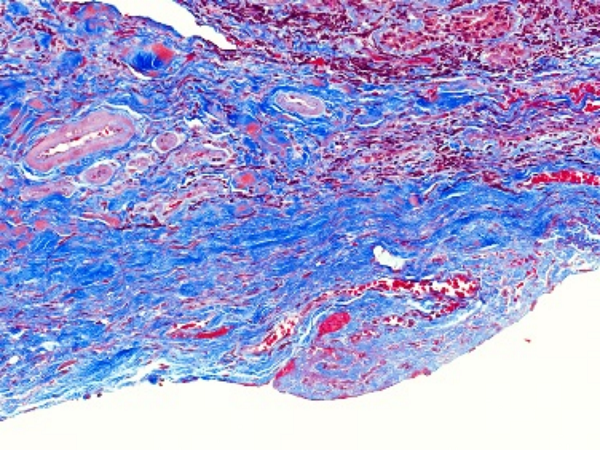

特殊染色是病理学和组织学中使用的一种染色方法,用于显示组织或细胞中的特定成分,这些成分在常规的苏木精 - 伊红(HE)染色中可能无法清晰地显示。以下是关于特殊染···...